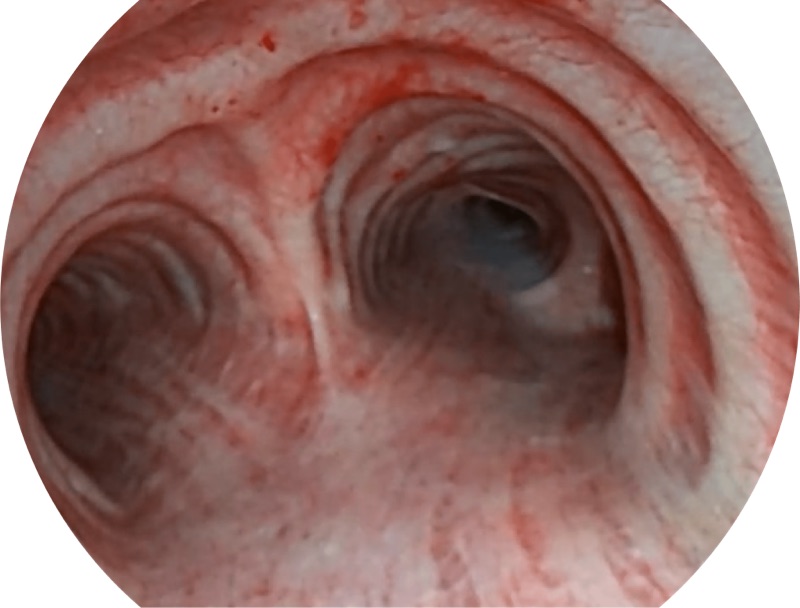

• 更细外径

EB-5H20具有4.9mm外径及2.0mm钳道提升对外围支气管检查能力